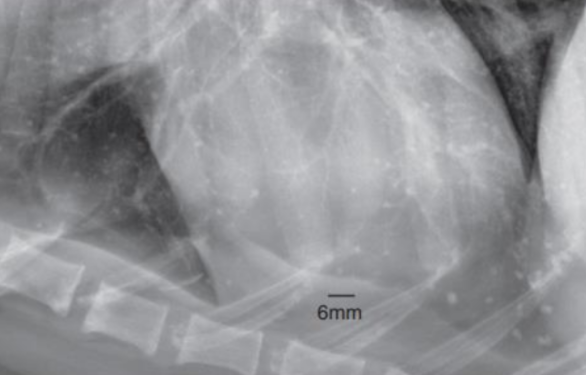

Pulmonary osseus metaplasia : ํ์ ์ํํ (๋

ธ๋ น์ฑ)![]() (ํ์ ์ด์ ๋นํด ๋๋ฌด ์๊ณ , opacity๊ฐ bone์ ๋ ๊ฐ๊น์) |